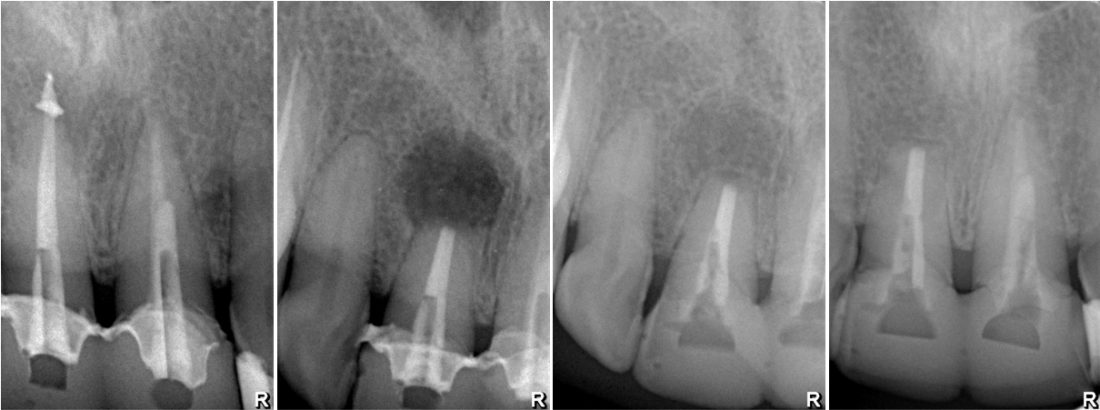

Фактически, хирург только создает условия, убирает раздражающий фактор - а далее организм всё делает самостоятельно. Наша задача - лишь помочь ему с этим справиться.